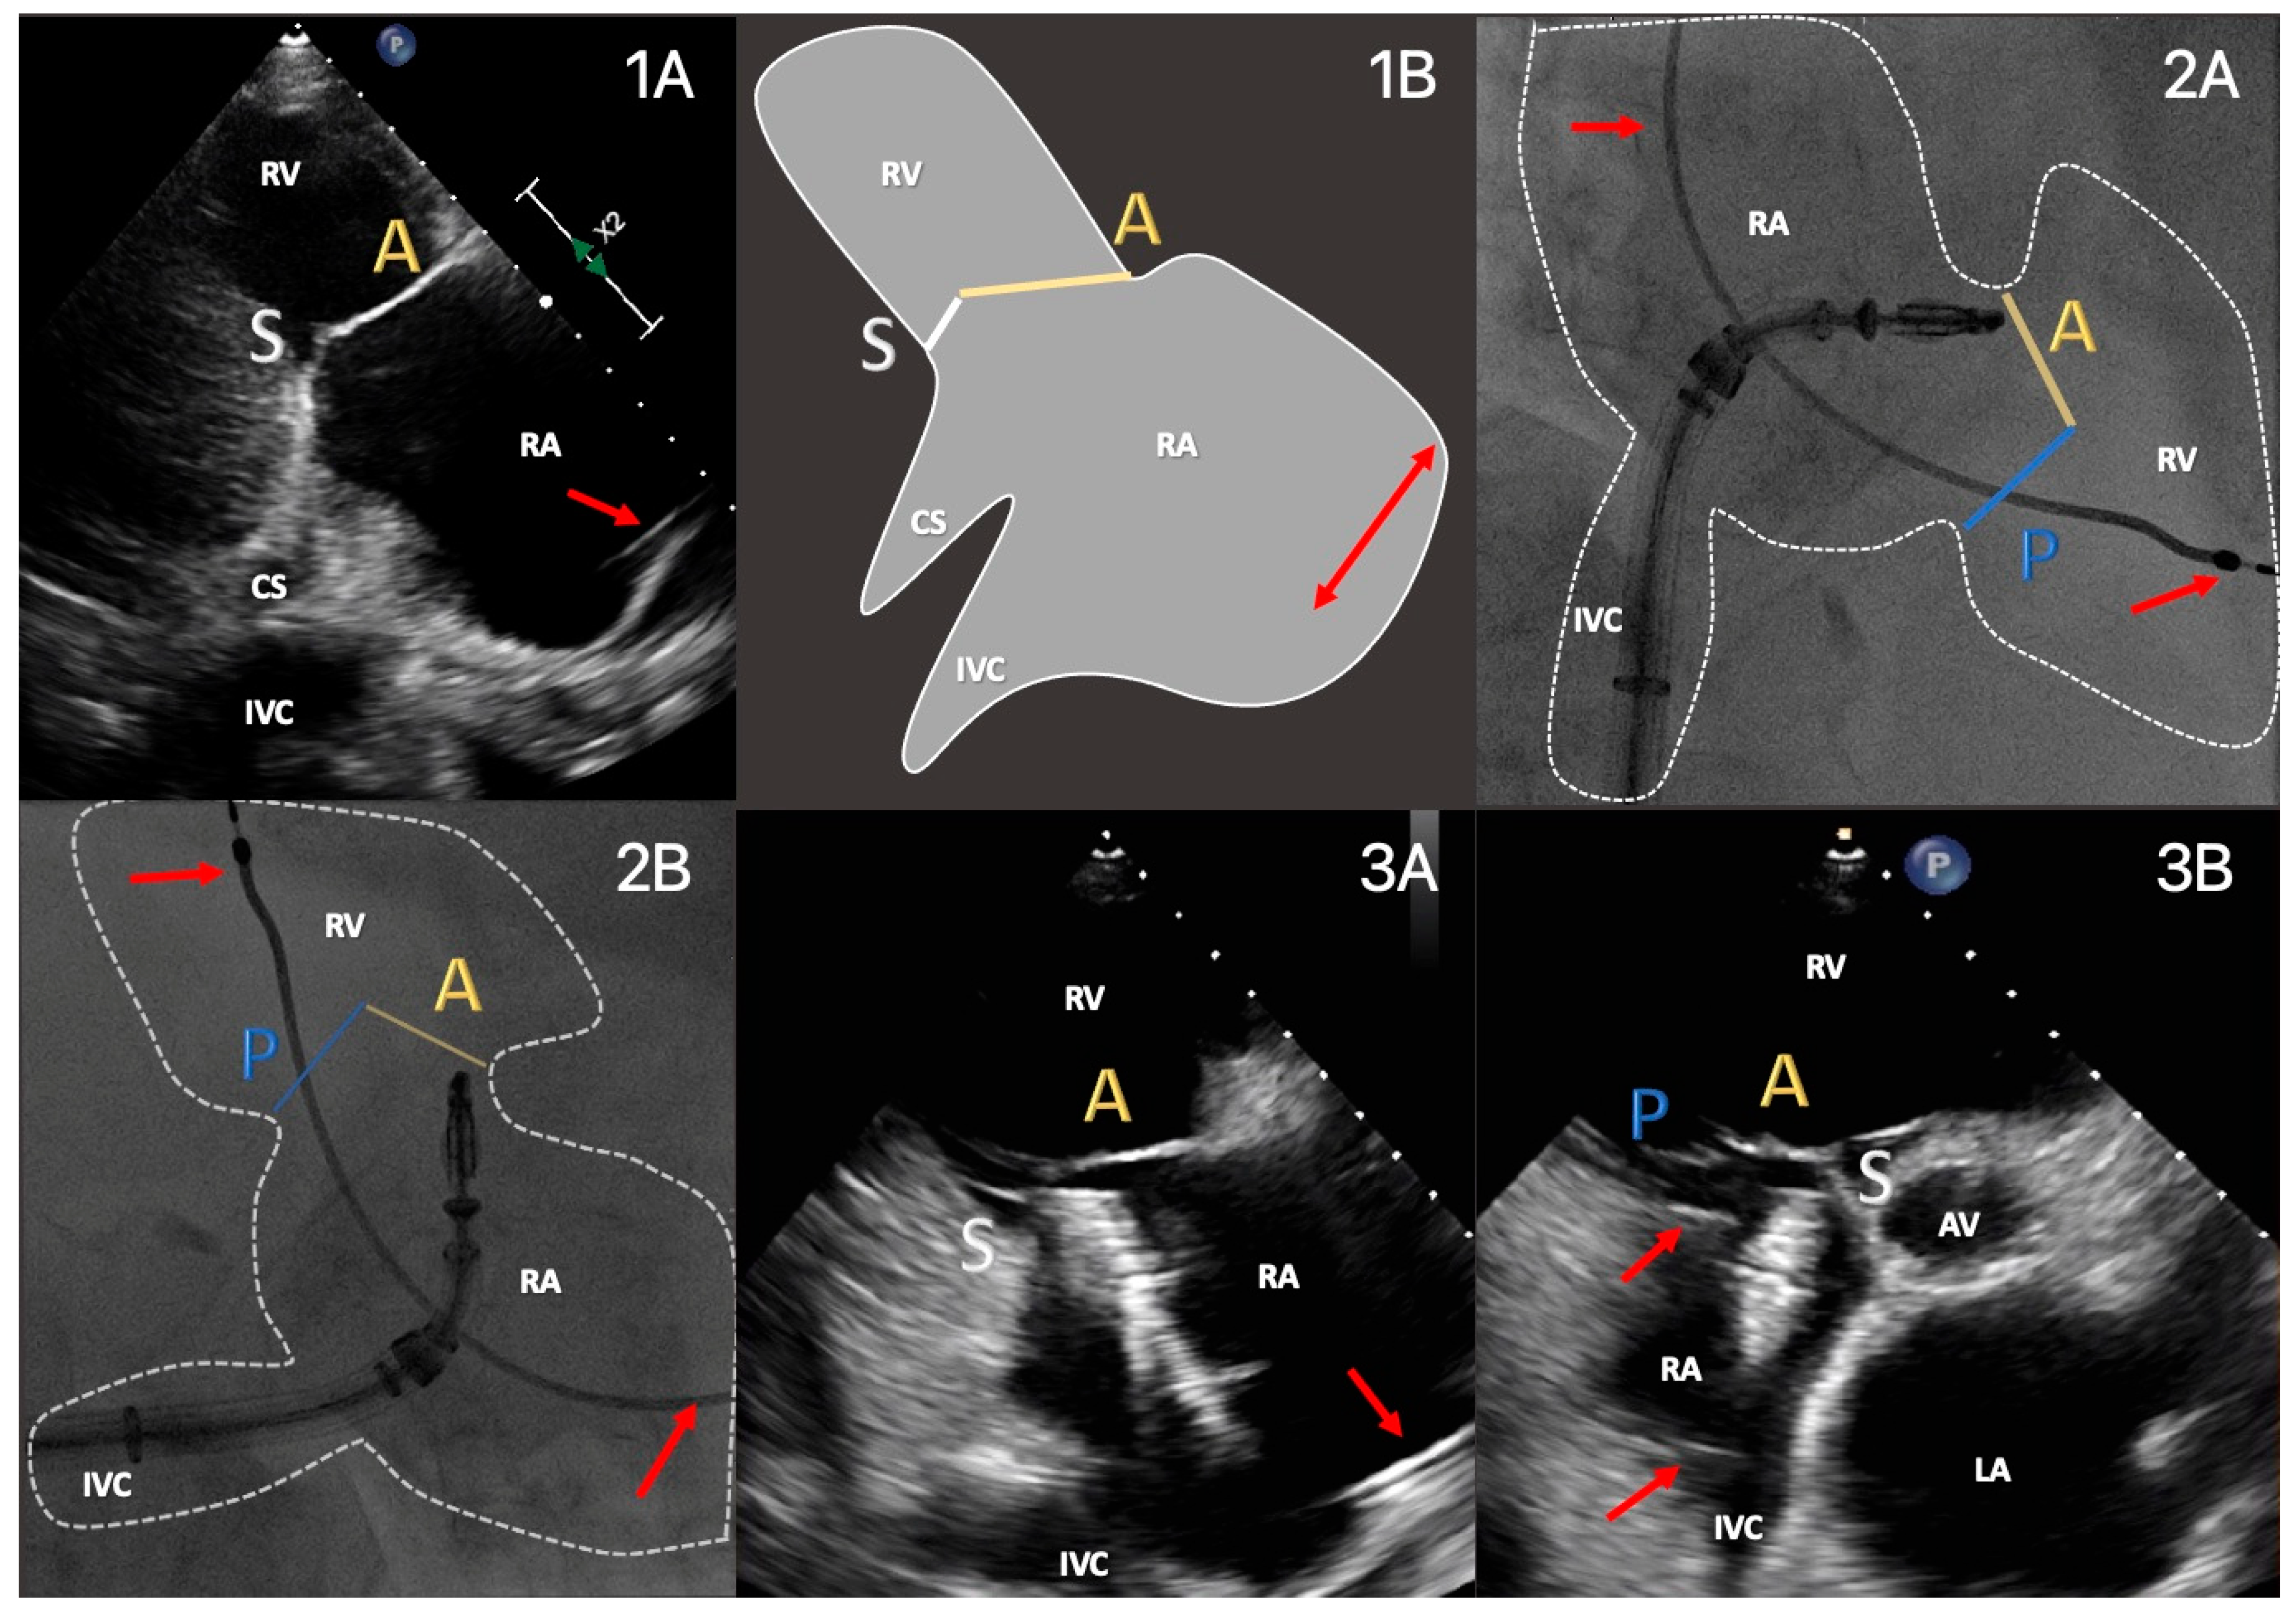

| TTE View | Focus | ||

|---|---|---|---|

| Functional Parameters | Right Heart Morphology | TV Anatomy | |

| PLA standard | LVOT diameter (Qs/CO calculation) | RV function and size (eyeballing) | -- |

| PLA RV inflow RH two-chamber view | TR severity (eyeballing) TR Jet VC and PISA (optional) | RV function and size (eyeballing) | AL visualization SL vs. PL distinction |

| PSA standard RH three-chamber view | TR severity (eyeballing) RVOT VTI RVOT diameter | RV size PA size | Leaflet distinction, if possible |

| PSA-modified alternative RH one-chamber view | TR severity (eyeballing) | TV annulus size Coaptation gap | Simultaneous visualization of all leaflets |

| A4C RH four-chamber view | TR Jet area, VC and PISA TR VTI, RVSP TAPSE RV free wall TDI RV FAC RA volume RV diameters LVOT VTI (A5C/A3C) | RV function and size RA size TV annulus size Tenting height | SL visualization AL vs. PL distinction |

| A2C right alternative RH two-chamber view | TR Jet area, VC and PISA | RA size TV annulus size | AL visualization |

| Subcostal long axis | Hepatic systolic vein flow reversal Inferior vena cava size | RV function and size (eyeballing) | PL visualization AL vs. SL distinction |

| Subcostal short axis RH one-chamber view | TR severity (eyeballing) | Coaptation gap | Simultaneous visualization of all leaflets |